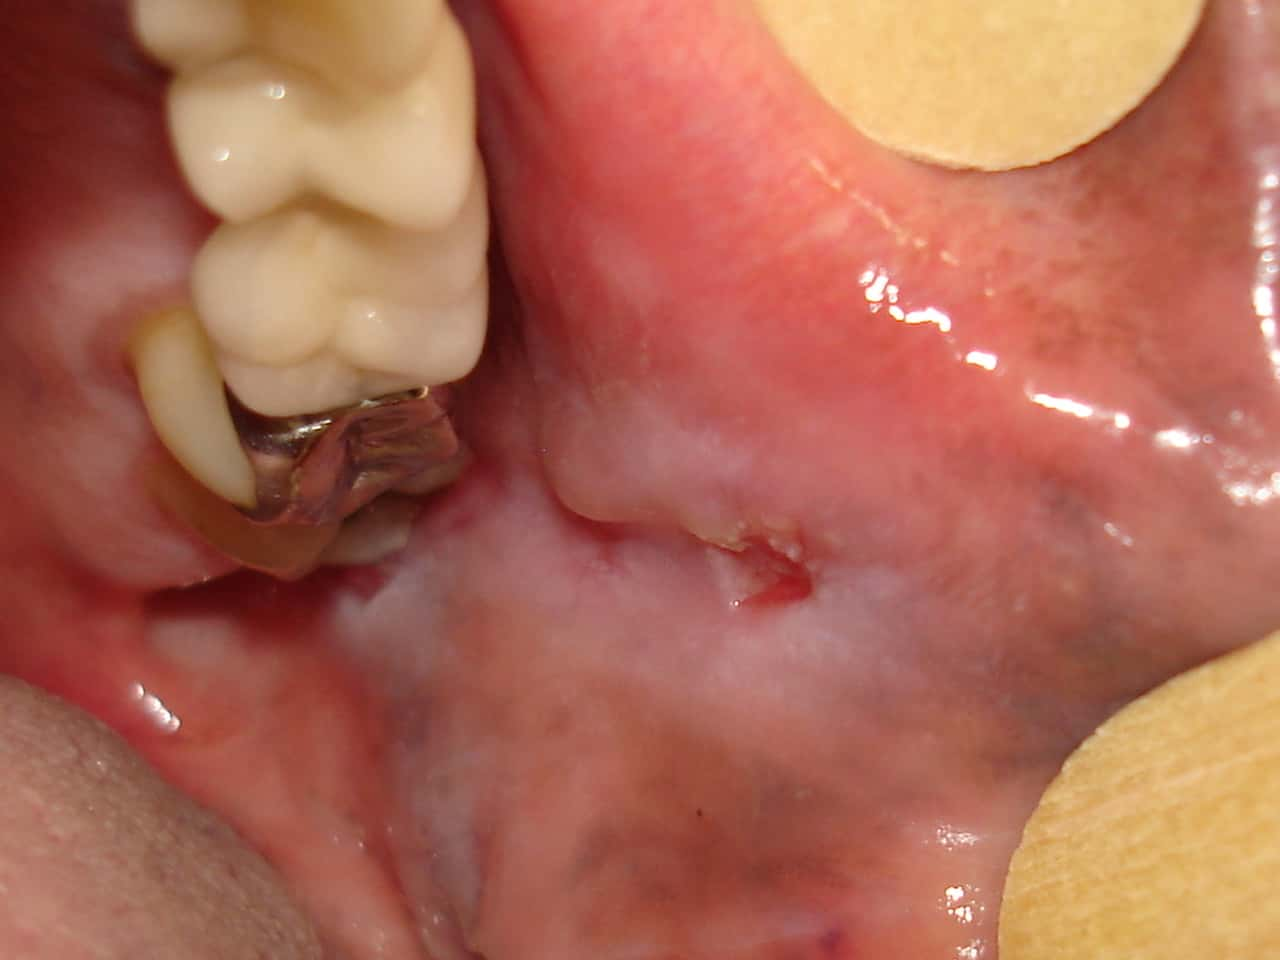

Úlcera Traumática em mucosa jugal